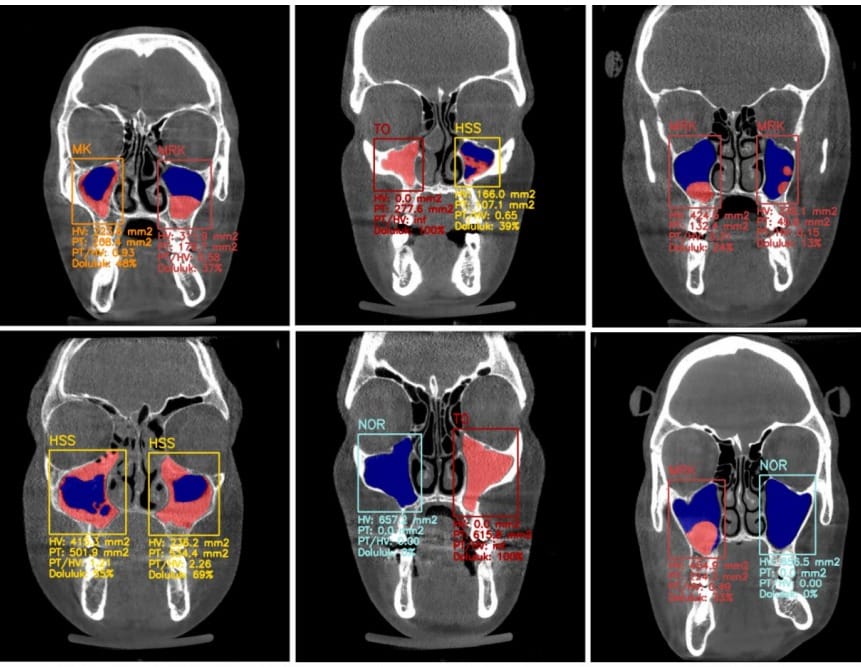

"Yapay zekayı sürece dahil etmemizin temel sebebi; insan gözünün kaçırabileceği milimetrik detayları yakalamaktır. Elde ettiğimiz veriler, yapay zekanın %99’a varan doğruluk oranlarıyla teşhis yapabildiğini gösteriyor. Bu, tıpta neredeyse 'sıfır hata' diyebileceğimiz bir devrimdir."

Türkiye’de uzman sayısı oldukça az olan Ağız, Diş ve Çene Radyolojisi branşının kritik önemine değinen Bulut, bu alanın çene ve yüz bölgesindeki karmaşık patolojilerin tespitinde anahtar rol oynadığını belirtti. Yapay zekânın, bir uzmanın yıllar içinde edindiği tecrübeyi standart bir diş hekimine aktarabilecek bir köprü vazifesi gördüğünü ekledi.

Kontrol ve imza yetkisinin her zaman insanda kalacağını belirten Bulut, özellikle nadir görülen hastalıklar ve sinüs patolojileri gibi uzmanlık gerektiren durumlarda YZ analizlerinin yanlış tedavilerin önüne geçeceğinin altını çizdi.